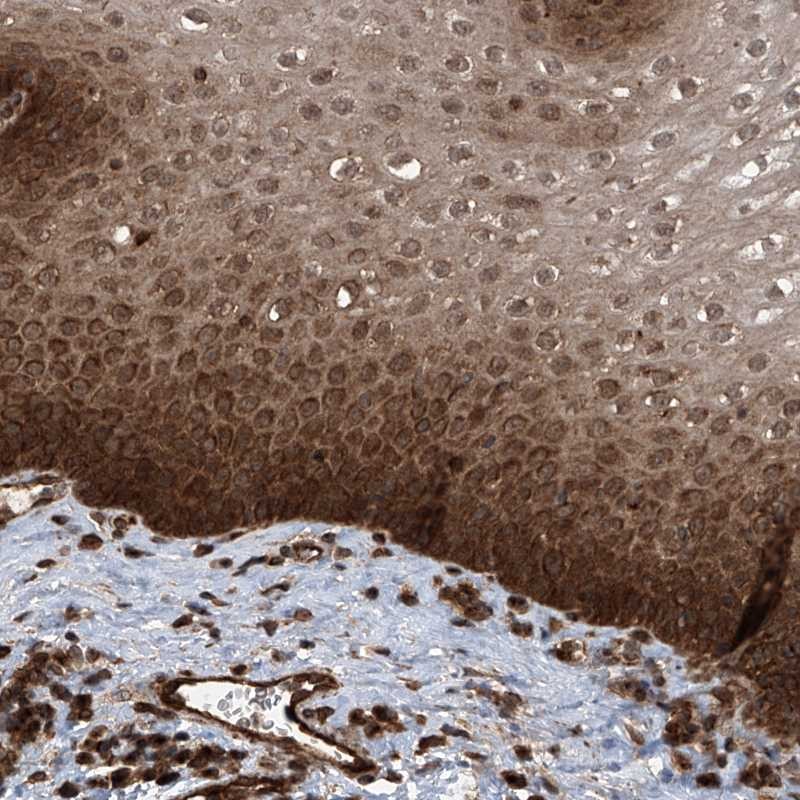

Immunohistochemical staining of human esophagus shows strong cytoplasmic and nuclear positivity in squamous epithelial cells.